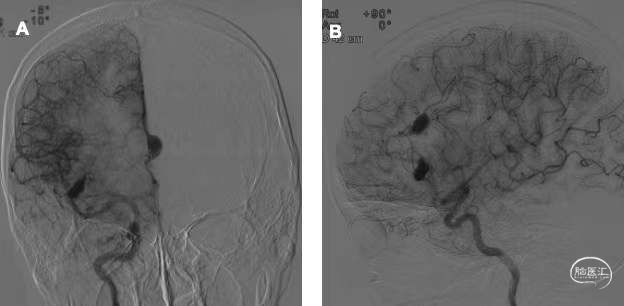

患者,女,58岁,因“体检发现颅内动脉瘤2年”收入院。2年前头颅MRI显示右额叶异常信号,当地医院考虑海绵状血管瘤,并予保守治疗。1年前有心房粘液瘤切除史,围手术期查头颅MRA显示右侧大脑前动脉及大脑中动脉各一枚梭形动脉瘤(图1)。本次入院前复查头颅MRA显示右侧大脑前动脉动脉瘤较前增大,要求手术而收入院。入院体格检查无神经系统阳性体征。

图1. 一年余前头颅MRA显示右侧大脑前动脉及右侧大脑中动脉远端梭形膨大(红箭头所示),动脉瘤远端血管显影良好。